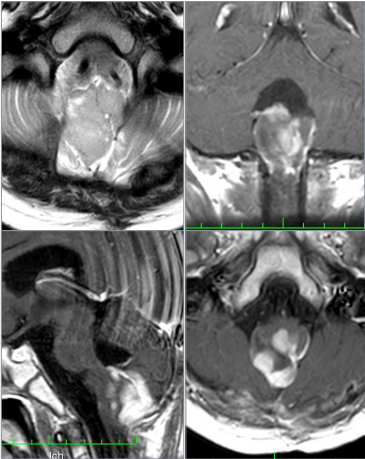

延髓膠質(zhì)瘤屬于腦干膠質(zhì)瘤的異質(zhì)組。這些腫瘤起源于髓質(zhì),并可延伸至鄰近結(jié)構(gòu),如腦橋、小腦下梗、小腦和脊髓上部。腦膠質(zhì)瘤發(fā)生在兒童和成人患者...